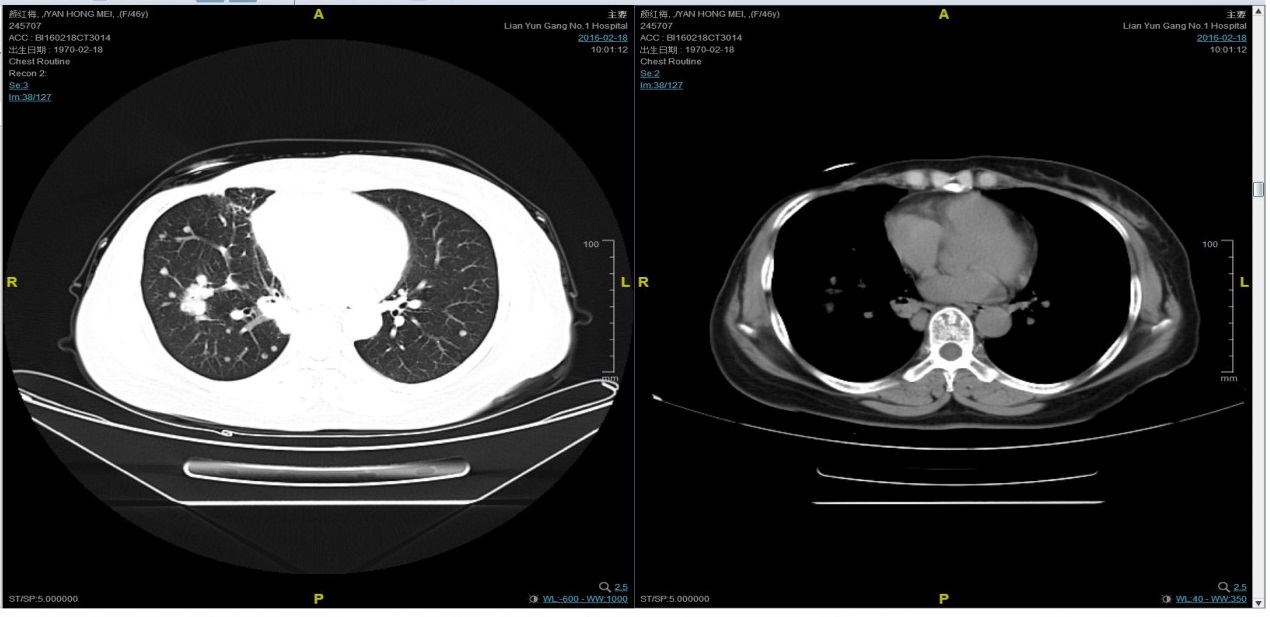

期间2016-4-22复查CT如下:

患者颜X X,女,发病年龄43岁。2010.12.01因体检发现右乳质硬、无痛性肿块住院治疗。入院查体肿块约2.5cm × 1.5cm。考虑诊断为右侧乳腺癌。2010.12.06在我院全麻下“右乳癌改良根治术”。术后病理:(右)乳腺浸润性导管癌,组织学分级Ⅲ级;乳头、皮肤未见癌累及,同侧腋窝淋巴结转移(19/19)。免疫组化:ER(-),PR(-),C- erbB-2(3+)。术后诊断右乳浸润性导管癌并右侧腋窝淋巴结转移(pT2N3M0,IIIC期,HER2阳性型)。术后于2011-01-06起在连云港市第一人民医院给予AC方案化疗4周期,2011-03-20给予右胸壁+右锁骨上下淋巴引流区放疗Dt50Gy/25f,2011-05-26予TH方案化疗4周期(曲妥珠单抗d1首次480mg,以后360mg)共4周期。后续予以曲妥珠单抗360mg(每21天为一周期)维持治疗1年,末次使用曲妥珠单抗的时间在2012年5月,后定期随访,病情稳定。2013-11-23全面复查发现肺转移。 DFS=35个月。2013-11-26起给予曲妥珠单抗(440mg d1)/脂质体紫杉醇(240mg d2)/CBP(500mg d2)方案化疗一个周期,出现Ⅱ度骨髓抑制,因患者主诉乏力明显,后修改方案曲妥珠单抗(330mg 每 3周重复)/脂质体紫杉醇(120mg d1+d8+d15,每4周重复)化疗,化疗过程顺利,患者无明显骨髓抑制,无乏力主诉,于2014-02-11全面复查,疗效评价为PR。继续曲妥珠单抗+脂质体紫杉醇(共六周期)治疗,疗效评价CR。后续予以曲妥珠单抗维持治疗,随访病情稳定。2015年4月,患者肺部病灶复发。给予曲妥珠单抗+希罗达治疗(希罗达1500mg,一天两次口服)。PFS1=17个月。2016-2-18,肺部病灶进展,肺内转移病灶增多。PFS2=10个月。从2016-2-19开始给予紫杉醇+曲妥珠单抗治疗,紫杉醇240mg,3周重复,曲妥珠单抗330mg三周重复。患者末次应用曲妥珠单抗和紫杉醇时间为2016-6-24,紫杉醇共应用4周期。CT评价SD。继续曲妥珠单抗维持治疗,且自服中药。2017-02-27患者因气喘胸闷再次就诊。患者肺部病灶进展,同时出现肝脏转移。再次给予曲妥珠单抗+长春瑞滨化疗一周期,效果不佳,患者放弃治疗。PFS3=12个月。